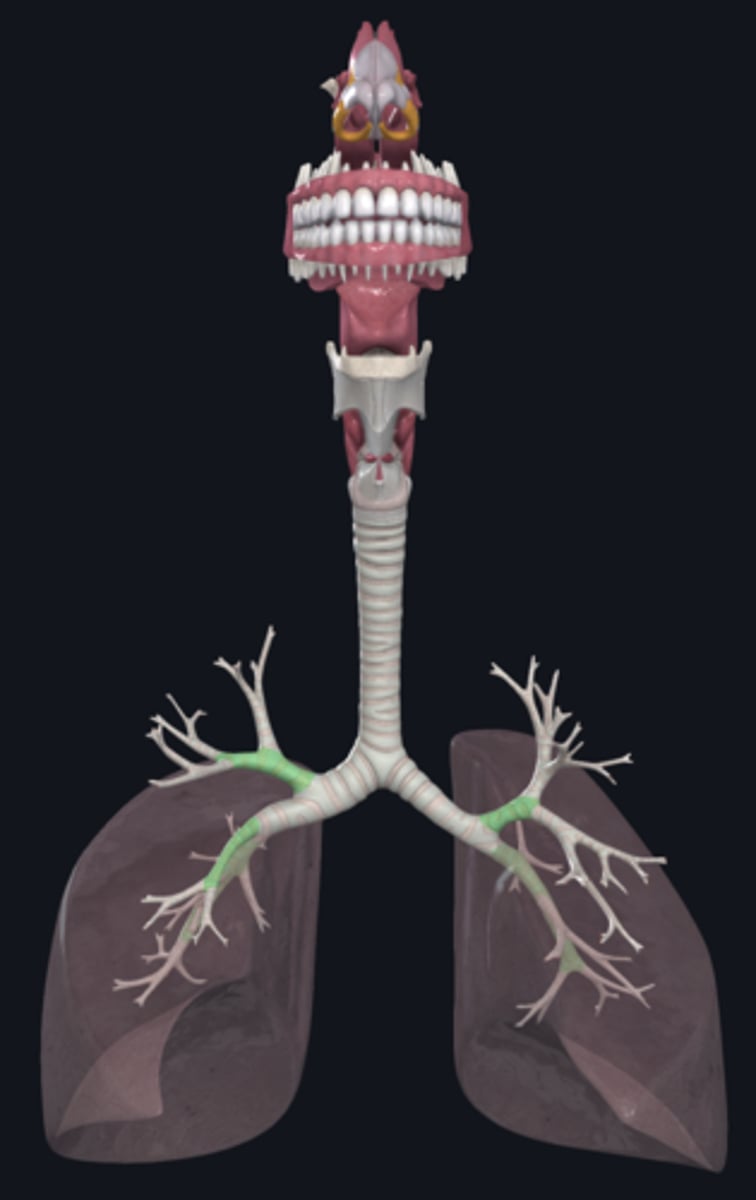

Week 10: Lungs & Airways

trachea

tracheal cartilage

trachea

tracheal cartilages

annular ligament

right main bronchus

left main bronchus

lobar bronchi

terminal bronchi

right lung

left lung